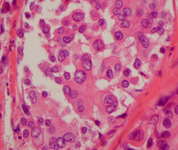

Histopatologia do carcinoma lobular in situ (CLIS) pleomórfico

Cortesia da Dra. Sunati Sahoo, Universidade de Louisville; usado com permissão